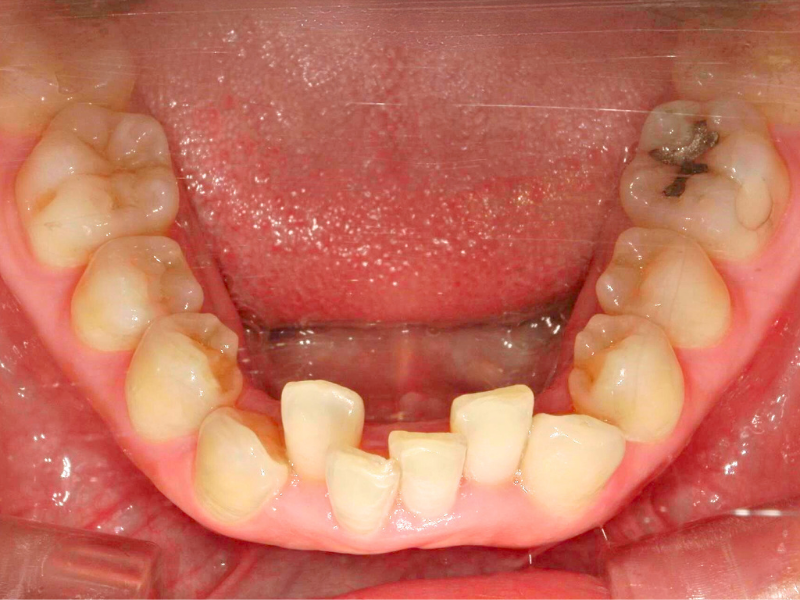

20代、女性、ワイヤー

| 施術内容 | 主訴:下の前歯の凸凹が気になる 詳細:ワイヤー矯正での歯並び改善 |

| 治療期間 | 4ヶ月(10/1現在 治療終了) |

| 費用 | 部分矯正 10万(税込110,000円) |